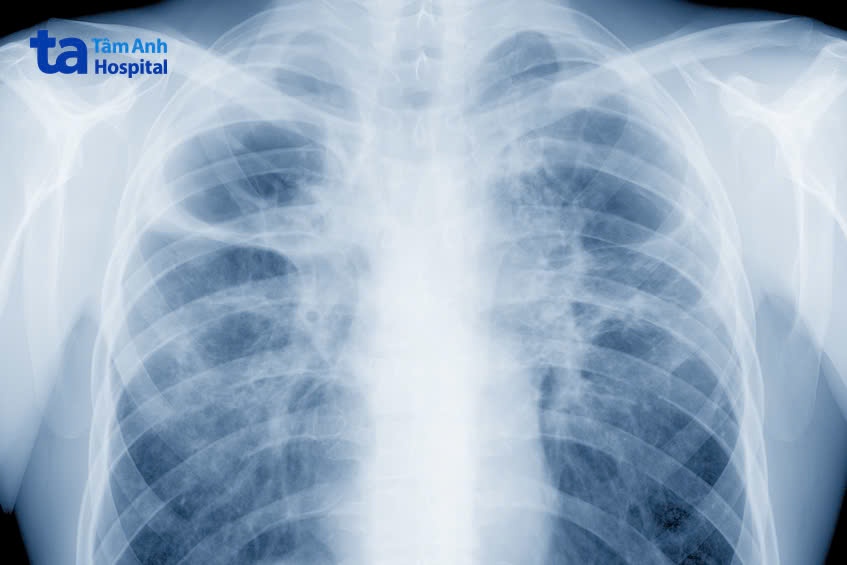

Các triệu chứng không đặc hiệu, trùng lẫn với các bệnh hô hấp thông thường khác, đặc biệt ở người cao tuổi có nhiều bệnh nền phối hợp, dẫn đến khó khăn trong tiếp cận. Do đó, để đoán chính xác bạn cần được thăm khám lâm sàng với bác sĩ chuyên khoa Hô hấp. Bác sĩ có thể yêu cầu bạn thực hiện một hoặc nhiều xét nghiệm: